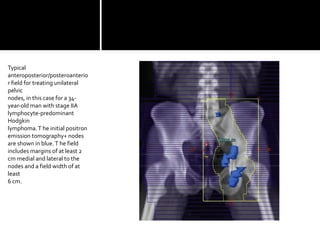

Typical

anteroposterior/posteroanterio

r field for treating unilateral

pelvic

nodes, in this case for a 34-

year-old man with stage IIA

lymphocyte-predominant

Hodgkin

lymphoma.T he initial positron

emission tomography+ nodes

are shown in blue.T he field

includes margins of at least 2

cm medial and lateral to the

nodes and a field width of at

least

6 cm.